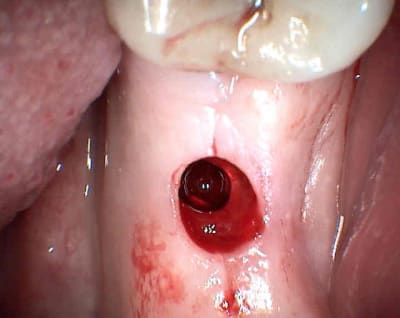

je relance le sujet

vu aujourd'hui patiente à qui j'ai posé il y à 5 semaines un axiom en 36 sans aucun soucis perop ni postop je la revois aujourd'hui elle présente un petit épulis crestal en regard de la tête de vis de cicat et petite perte crestale

je lui mets la vis haute demain pour dégager autour de la tête cette zone inflammatoire et ou infectieuse.